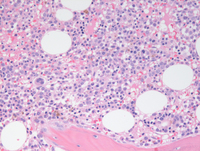

Bone marrow biopsy findings

Bone marrow biopsy demonstrated about 50-60% cellular marrow (otherwise almost normocellular for age) with evidence of an increased mononuclear blastic component percolating throughout the interstitium at higher power (image of the right side).